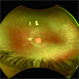

- Both the right and left Eye have fairly symmetrical, extrafoveal drusenoid-like flecks and focal and faint areas of RPE hyperplasia (in addition to mild NPDR and PPA) 57 yo WF referred for AMD vs Pattern Dystrophy that was diagnosed 10 years ago. Reported some slow progressive vision loss in both eyes for distance and near. Denies nyctalopia or hemeralopia. Background medical history includes HTN, CVD, and DM. No family history of eye problems. Denied pentosan use. Anterior segment showed moderate cataracts (OD>OS). Posterior segment exam showed macular changes and mild NPDR. The macular appearance showed a symmetrical, paramacular ring of fleck-like drusenoid material with some faint focal areas of RPE hyperplasia. Fundus Photos, AF, OCT were performed as well as a gene test. Further questioning showed revealed that her mother and maternal grandmother had both diabetes mellitus and sensorineural hearing loss. The patient developed diabetes in her teens, and some high frequency hearing loss in her early twenties. She had not had a previous genetic test or diagnosis of MIDD. Gene testing is pending for the mitochondrial component. Invitae's retinal panel, which does not include mitochondrial disorders, only showed a variant of uncertain significance, HMCN1. I discussed this case with Dr. Freund, and it is similar to a the case report : Inoue M, Kiss S, Freund KB. MACULAR PIGMENT RINGS AS THE PRESENTING FINDING OF MITOCHONDRIAL MYOPATHY, ENCEPHALOPATHY, LACTIC ACIDOSIS, AND STROKELIKE EPISODES. Retin Cases Brief Rep. 2015 Fall;9(4):260-4. doi: 10.1097/ICB.0000000000000182. PMID: 26200388.